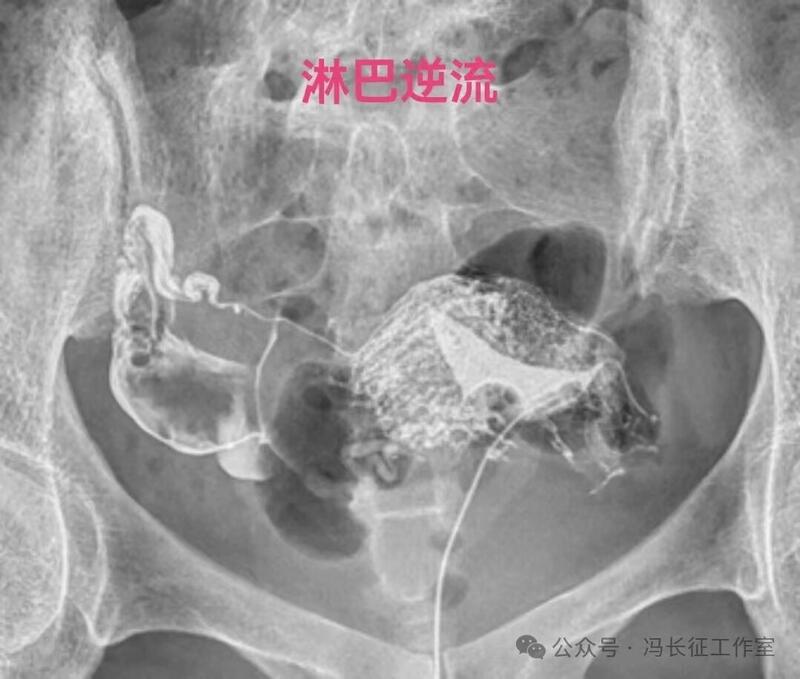

在子宫输卵管造影,用碘油做造影剂当出现逆流时立即停止造影检查,避免更多碘油进入静脉造成肺栓塞是正确的。但是,当用的造影剂是碘水时,出现逆流时还是可以继续进行造影检查,最终完成造影检查,尽量给被检查者一个完整的检查。千万不要听所谓的砖家乱讲,当发现有造影剂进入间质或血管,应立即停止造影。我们大家都知道成人在做CT增强检查时,常规用高压注射器直接从静脉注入约100毫升含碘水剂进行检查几十年了,因此,碘水是可以进入静脉和淋巴的。一般子宫输卵管造影所用含碘水剂20毫升左右,即使20毫升含碘水剂都逆流静脉不会对身体有啥影响的。因为含碘水剂主要经肾从尿液排出体外,有时还相当于免费送一个静脉肾盂造影检查。

造影剂逆流可以进入静脉和淋巴管,逆流分三种:(1)淋巴逆流;(2)静脉逆流;(3)淋巴和静脉混合性逆流。其实,一般多是静脉和淋巴都有的混合性逆流,淋巴逆流是造影当时以淋巴逆流为主,同时有少量的静脉逆流,本来淋巴管后来就是要汇入到静脉的。静脉逆流也是以静脉逆流为主,同时有少量的淋巴逆流。